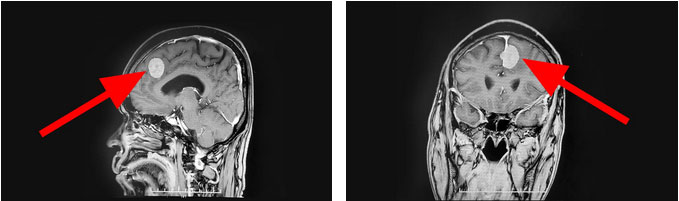

頭顱MR顯示,患者左側(cè)額部大腦鐮旁可見一塊團(tuán)狀異常信號影,大小約2.2cm*2.1cm *2.6cm,伴有腦水腫。由神經(jīng)外科6B病區(qū)主任潘仁龍、李士其教授、吳治群博士組成的專家組會診后指出,患者顱內(nèi)占位明確,根據(jù)影像學(xué)表現(xiàn)考慮為左側(cè)額部大腦鐮旁腦膜瘤。腫瘤的體積較大,相鄰腦組織受壓明顯,應(yīng)盡早接受手術(shù)治療。

▲ 腫瘤位于左側(cè)額部大腦鐮旁